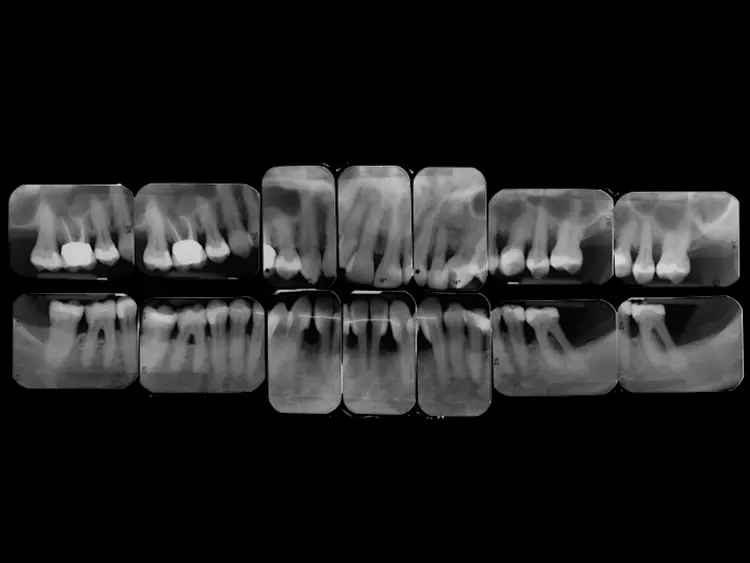

Der extraorale Befund war unauffällig. Der intraorale Befund (Abb. 2) zeigte eine lückenlose Dentition und eine verbesserungsbedürftige Mundhygiene (PI: 37%, BI: 2%) auf. Die Zähne 14 und 23 fehlten aufgrund einer Nichtanlage.

Einige Zähne waren konservierend suffizient versorgt (Abb. 3). In der Unterkieferfront bestand ein ausgeprägter Engstand mit Verschachtelung (Crowding).

Im Seitenzahnbereich bestanden an zahlreichen Zähnen Furkationsbeteiligungen. Die Zahnbeweglichkeit war an 2 Zähnen deutlich erhöht. An mehreren Zähnen lagen zudem gingivale Rezessionen vor.

- Generalisierter horizontaler Knochenabbau

- Lokalisierte vertikale Knochendefekte bei den Zähnen 22, 35, 32 und 42

- Radioluzenz im Furkationsbereich der Zähne 36, 46